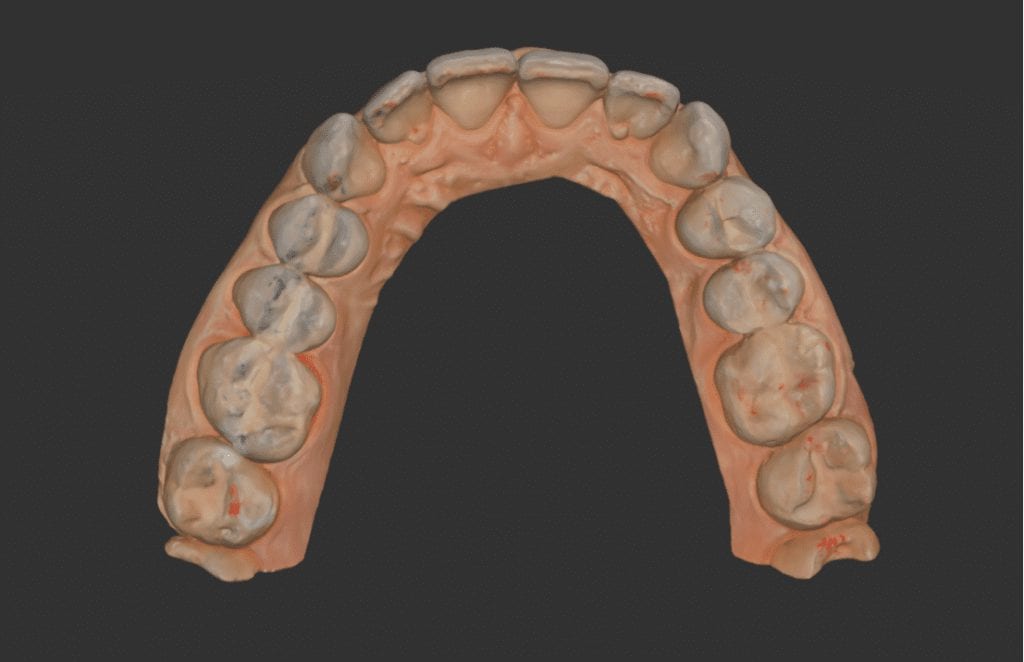

In this particular clinical case, the patient has opted to utilize clear aligners to straighten some anterior crowding. The Medit i500 was used to capture both the upper and lower jaws, and articulating paper was used to marked the clinical contact points.

In this video, you can see how we verify the accuracy of the occlusal contacts. In the software, you can open the articulated arches and look for contact points made digitally and you can compare those to the clinical marks left with articulating paper.